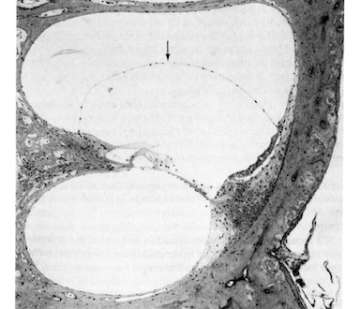

Endolymphatic hydrops are seen in middle turn of chinchilla cochlea four weeks following endotoxin instillation into the bulla

(B) Endolymphatic hydrops (arrow) are seen in middle turn of chinchilla cochlea four weeks following endotoxin instillation into the bulla. No cellular infiltration is seen in the perilymphatic space.